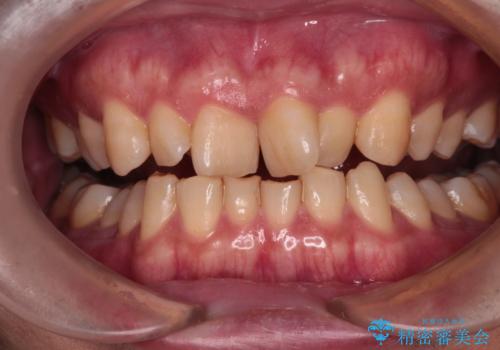

- 深い咬み合わせと上顎前歯の突出感を気にして来院された患者様です。

当院では通常、臼歯の咬合が理想的な位置に対して上顎が前方位にある場合。ワイヤー矯正または補助装置の併用したインビザライン矯正を選択しています。

今回は、できるところまででいいのでインビザライン単体で治療をしたいという希望があったため、インビザラインにて矯正治療を行うこととしました。